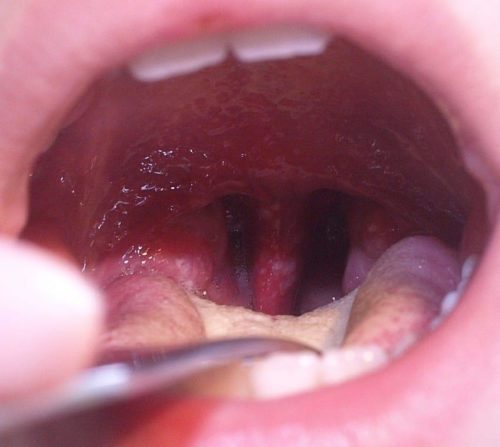

Tal vez muchas personas tengan este virus y lo confundan con un dolor de garganta o un resfriado. pero lo que caracteriza a este problema de salud son las manchitas de color rojo que suelen aparecer en la cavidad bucal, las palmas de las manos y las plantas de los pies de la persona que está infectada.

Se han registrado casos en los que los síntomas se agravan y aparecen úlceras distribuidas en distintas partes del cuerpo, en el peor de los casos, en los genitales.